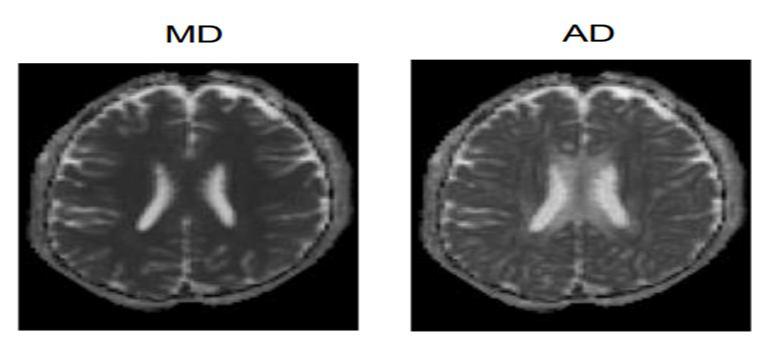

Fig. 5 RD and FA maps Fig. 6 MD and AD maps

In a similar manner, MD maps place an emphasis on inverse membrane density, which is determined by cerebrospinal fluid and the bright signal on the images indicates either a lower water diffusion or a larger water content, both of which are very helpful in the process of clinical assessment.

Fig. 9 Output MD map

When it comes to AD and RD maps, we are able to identify changes in the axonal parameter by adjusting the white matter area. This allows us to better understand the connections between neurons. In AD, the main water movement is strongly focused, along primary axis. but in RD, it is focused transverse to the long axis.

Fig. 10 Output AD map